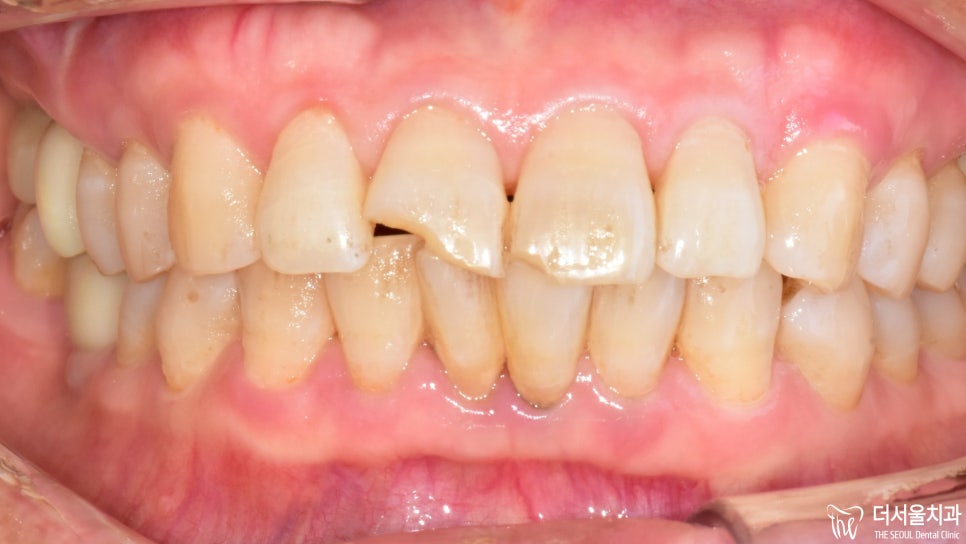

『 치아가 깨졌다?! 』 젓가락을 잘못 씹거나, 큰 충격을 받은 경우 혹은 충치로 인해 부식되었을 때는 이가 깨질 확률이 높아지게